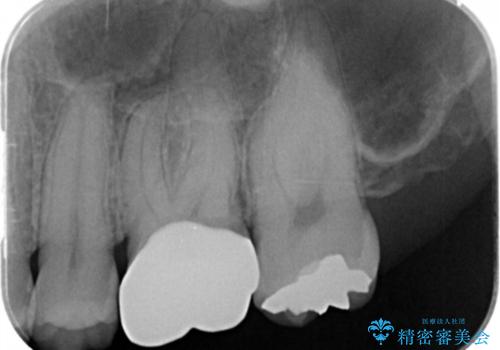

- 詰め物が欠けたとの事で来院。

口腔内を確認したところ詰め物が欠けていたのではなく歯質がう蝕により欠けていました。

拡大鏡下でう蝕を全て取り除き、フルジルコニアクラウンで治療を行いました。

無事う蝕を全て取り除き、適合の良い白い被せ物が入りました。